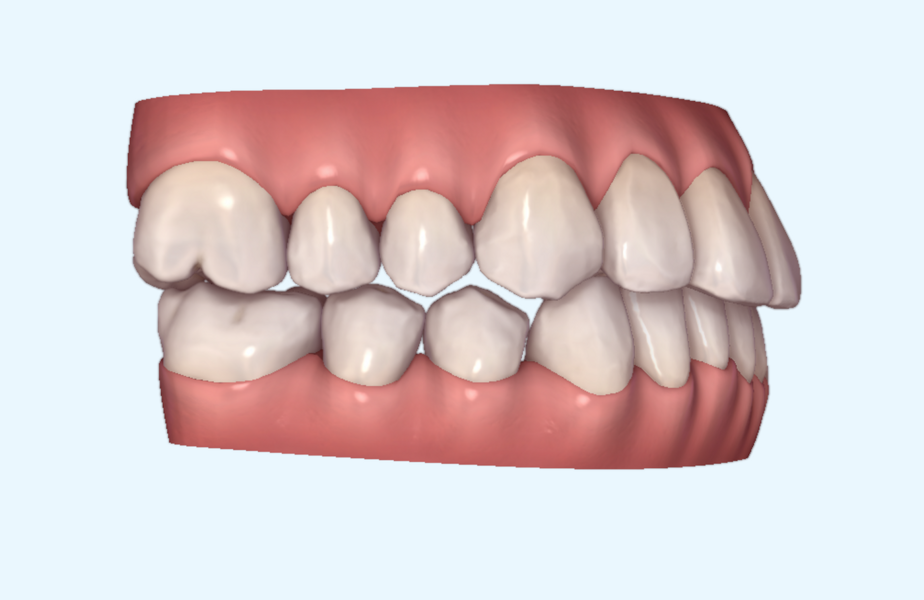

This patient, like all patients requiring interdisciplinary rehabilitation, had to first undergo periodontal treatment and caries restoration (Fig. 17). At the same time, it was important to rehabilitate swallowing with Froggymouth and relax the masticatory muscles and relieve the TMJs with an occlusal device. We could then study the orthodontic treatment plan using Invisalign ClinCheck (Align Technology) and showed the treatment plan to the interdisciplinary team and to the patient (Fig. 18). We were then able to create the correct sequence of orthodontic treatment, bone augmentation and implant surgery needed for the posterior edentulous spaces.

After the first phase of aligner treatment, we had achieved better inter-arch coherence, better maxillary arch expansion, and some space for improving the anterior tooth proportions restoratively (Fig. 19). We then temporarily restored the anterior teeth directly with composite, closing the spaces, improving the tooth proportions and further increasing the maxillary arch expansion (Fig. 20). We used restorative arch expansion to reduce the orthodontic destabilisation of the teeth to achieve the correct inter-arch coherence and retain the teeth in the cortical bone.38 A refinement aligner phase was undertaken to improve the final alignment of the gingival zenith and to improve the inter-arch coherence (Fig. 21). The periods of the first orthodontic phase and of the refinement were used to augment the mandibular and maxillary bone and to place the implants (Fig. 22). At the end of the orthodontic treatment, the case was finalised with ceramic veneers in the anterior area and temporary restorations on the implants in the posterior area (Figs. 23–26).